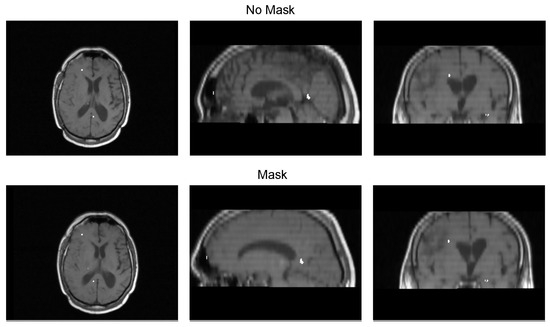

We validated the performance of the fusion method following the two methodologies in Section 3. We used eight pairs of CT and MRI from the RIRE dataset for the first method. The CT images were generated with the method described in Section 3.1.1. We compared the procedure shown in Figure 8 against a fusion procedure that does not employ a sampling mask of the brain tissue, which is shown in Figure 9. Both methods used a rigid registration with MI as the similarity metric and gradient descent for the optimization. We used descriptive statistical metrics of central tendency and variation to compare the methods using the validation from Section 3.1. These results were summarized in the box plot shown in Figure 10. For the second validation, we faced a limitation in the number of images available for evaluation. Given this constraint, we opted to compare the methods individually for each of the four cases. A scatter plot was chosen as the most suitable representation to visualize the error dispersion for both methods. Scatter plots are particularly effective in such scenarios as they allow for clear visualization of individual data points, making it easier to discern patterns or anomalies, especially when dealing with a smaller dataset. This approach provides a more transparent and detailed view of the distribution of errors across the limited set of images. The results of this comparison are illustrated in Figure 11.

Table 3 displays the Euclidean distance between the reference points and the resulting points of the transformation from the compared methods. From the data, we can observe that the difference in the Euclidean distance for our method is significantly lower in images 3, 6, and 8. This is mainly caused by the differences in the original images that have some variations in brain tissue, as shown in Figure 12, Figure 13 and Figure 14. Due to some electrodes passing through these areas with variations, the sampling in the registration does not use these voxels to compute the transformation, thus improving the registration when the mask is used. The results are represented in Figure 10, where our method using a sampling mask yields a Euclidean distance of 1.3176 mm with a standard deviation of 0.8643. In contrast, the method without a sampling mask yields a Euclidean distance of 1.2789 mm with a standard deviation of 5.2511. These findings suggest that the use of the mask improves the registration when there is a great difference in the tissue between the MRI and CT images due to the reduction in voxel sampling of these varying tissues in the registration process.

Figure 12. Image 3 fusion with no mask and with a mask.

Diagnostics 13 03420 g012